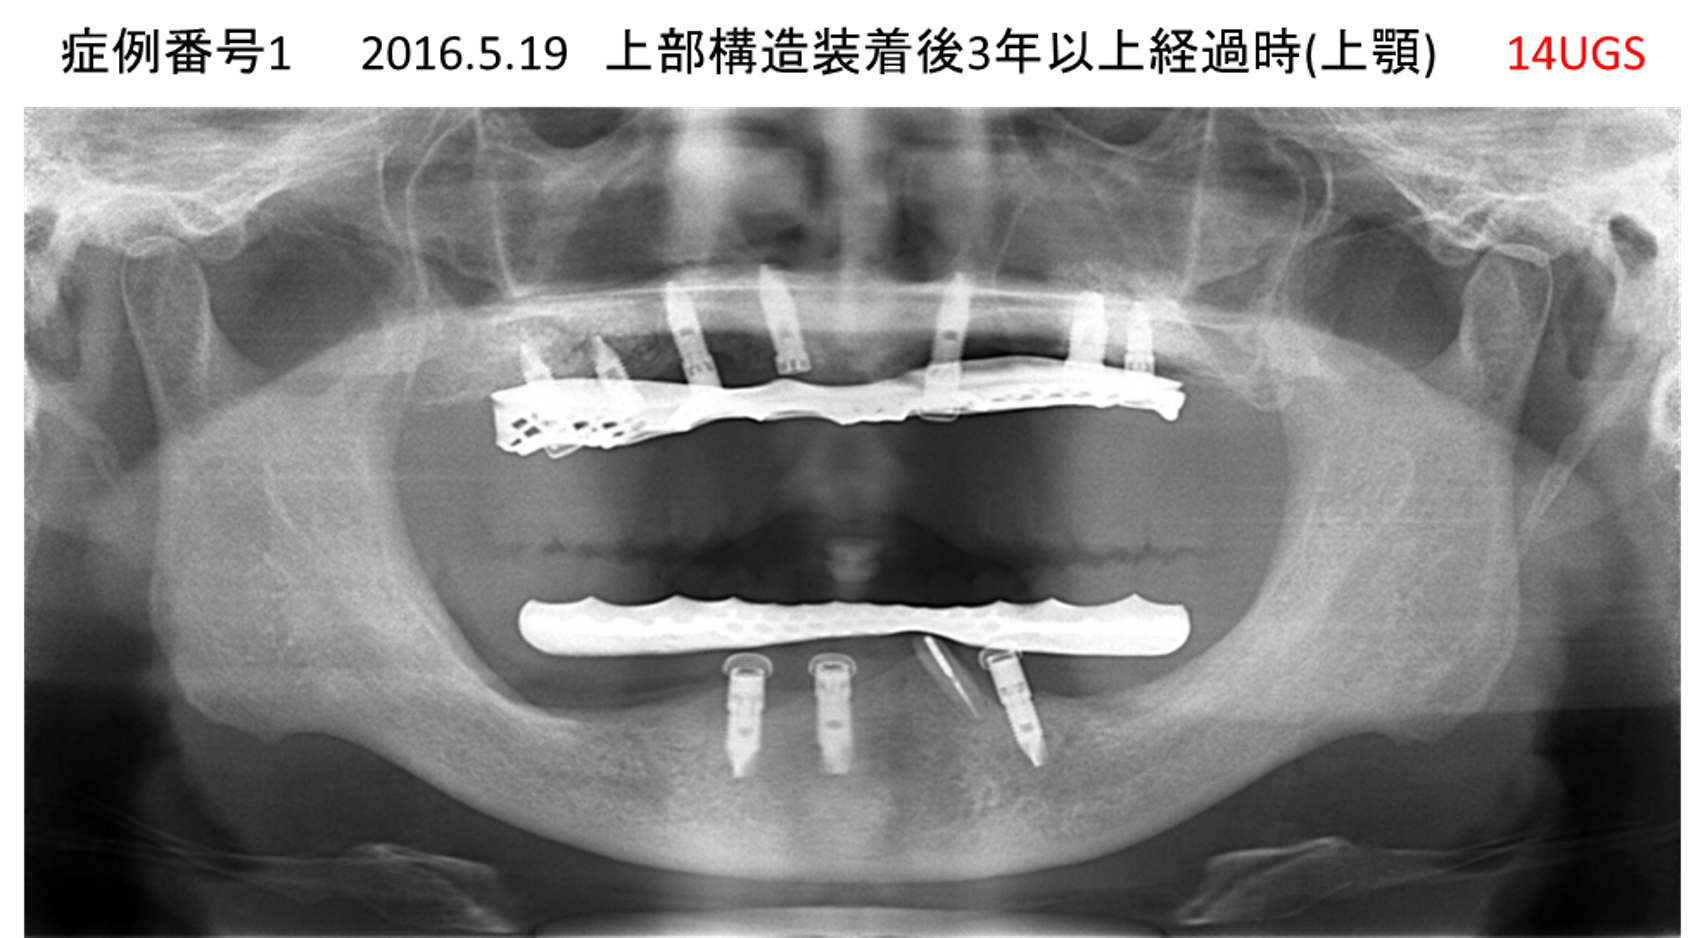

全く噛めない患者様のインプラント症例

| 治療名称 |

インプラントAGC |

| 治療費用 |

860万円+税 |

| 治療期間 |

12か月 |

| 患者さんの症状(主訴) |

全く噛めない、ごはんが後もに食べられるようになりたい、人前で口元を隠したくない |

| 治療内容 |

サイナスリフト、GBR、インプラント、AGC |

| 治療結果 |

しっかり噛めて踏ん張ることができる。食べ物をを選ばなくて済む、何でも食べられる、体重が増えた。見栄えがきれいすぎて自分じゃないみたい |

| 治療の注意点(リスク/副作用) |

インプラントが壊れたら再治療が必要 |